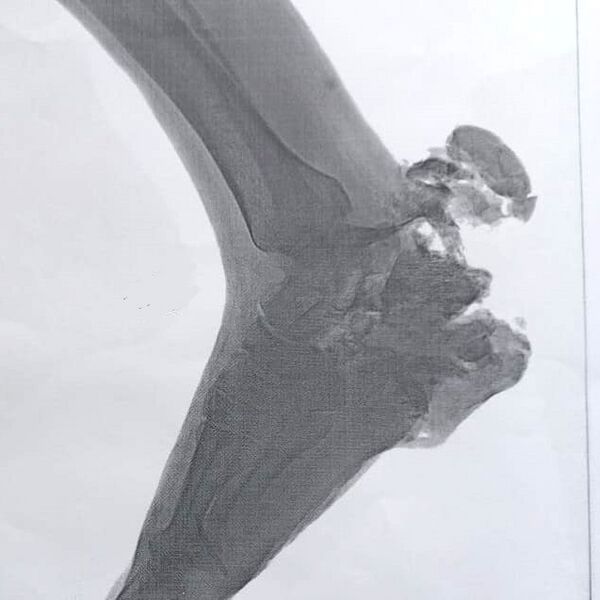

Поражение человеку при взрыве мины наносится за счет разрушения нижней части ноги. Взрыв производится в момент наступания ногой на нажимную крышку мины.

Мина ПМН принята на вооружение в 1950 году. Экспортировалась в различные страны мира и широко применялась в вооруженных конфликтах. За причиняемые человеку при взрыве тяжелые ранения, практически не оставляющие ему шансов остаться в живых, на Западе получила название «Чёрная вдова». С 1963 года производилась в Китае под индексом «мина типа 58».